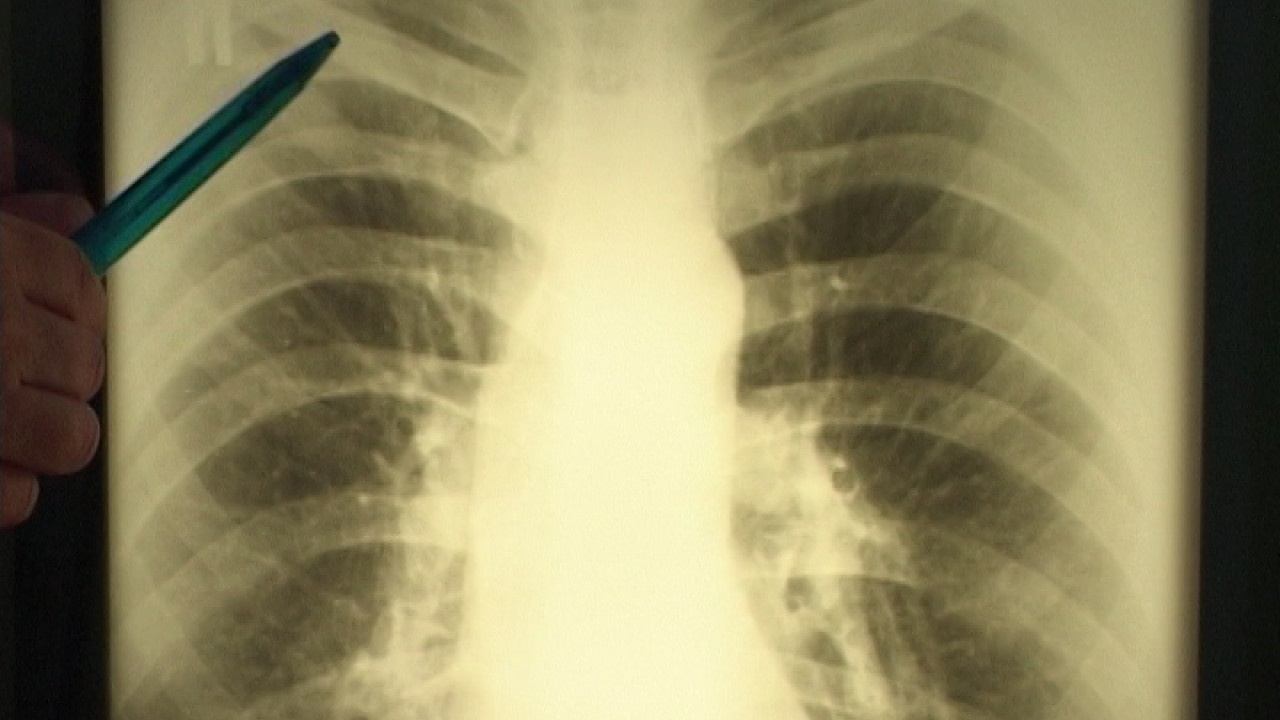

Ежегодно 24 марта в мире по инициативе Всемирной организации здравоохранения (ВОЗ) проводится Всемирный день борьбы с туберкулезом. Именно в этот день в 1882 году в Берлине доктор Роберт Кох объявил об открытии этой страшной болезни, которая до сих пор угрожает каждому из нас. Ситуация с распространением туберкулеза в Ирбите неблагоприятная, процент заболевания очень высок, сообщили нам врачи-фтизиатры.

Как говорят врачи-фтизиатры, неблагополучную ситуацию по туберкулезу можно изменить. Достаточно проводить стопроцентное флюорографическое обследование всего населения. Ведь только на ранних стадиях туберкулез хорошо лечится.